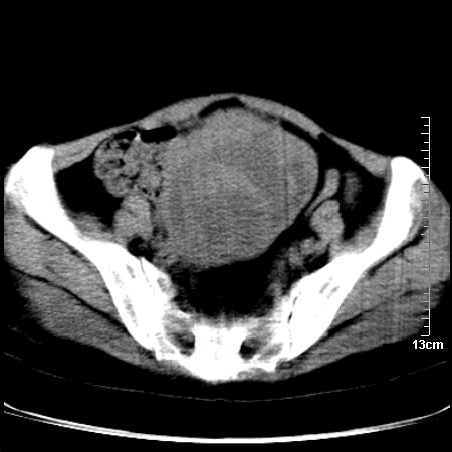

术前的疏忽,手术前诊断阑尾炎,但是没有常规做b超,导致术后1周检查发现 1。实性包块?2。腹腔术后脓肿?

病史:病人一周前诊断阑尾炎,未做b超,手术发现阑尾化脓,(没有留意有无包块),术后1周病人发热,血象:1.6万,做b超发现,随ct检查,上传图片

巨大囊实性包块,边界大部尚清楚,不太像脓肿的表现。应该做个增强检查除外盆腔肿瘤。

脓肿可能性大. 因回盲部区域化脓性兰尾切除残端感染改变征像与实性肿块关系密切.肿块上界至右下腹,下界至盆腔膀胱上缘, 如果是实性肿块在兰尾术中可能就会发现. 所以术后一周病人高烧, 白细胞增高,临床表现支持脓肿.

盆腔一边界大部份清晰囊实性肿块,其周腹脂未见确切异常,其一端与右侧附件相连。考虑右侧附件肿瘤。

如果能进行肠道准备就好了!盆腔内巨大囊实性包块,右前缘与周围肠管分界不清,病灶内前部的气体是否为肠管内气体形成的假象不能确定。

这么大一包快手术当中没有发现?值得怀疑!结合化脓性阑尾炎病史,首先考虑脓肿!不排外附件来源的肿瘤,建议增强扫描!!